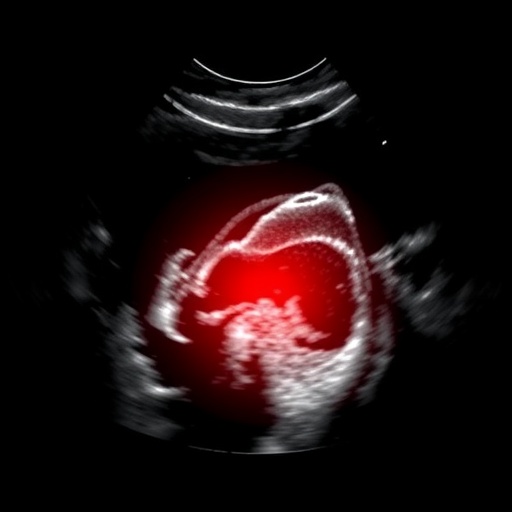

The significance of ultrasound in pediatric care cannot be overstated. Children are not merely little adults; their physiological responses and presentations can differ significantly from those of older patients. In cases of abdominal pain, distinguishing between benign and serious conditions promptly is paramount to ensure appropriate management. The ability of ultrasound to visualize organs and potential pathologies in real-time enables clinicians to make swift decisions regarding the necessity for surgical interventions or further investigations.

A striking finding from the research underscored the high sensitivity and specificity of ultrasound in detecting various abdominal pathologies. For instance, in cases of suspected appendicitis, ultrasound proved to be an invaluable tool, enabling clinicians to identify inflamed appendices with remarkable precision. The nuances of such findings were discussed in detail, noting that the absence of inflammation on ultrasound could effectively guide clinicians away from unnecessary surgical explorations, thus reducing morbidity associated with surgery.

One cannot overlook the implications of time efficiency in acute settings. The rapid turnaround time for ultrasound results can vastly improve the management of acute abdominal pain. In their findings, the authors emphasized that the swift diagnosis afforded by ultrasound could lead to timely interventions and improved outcomes, particularly critical in cases involving conditions like torsion or perforation.